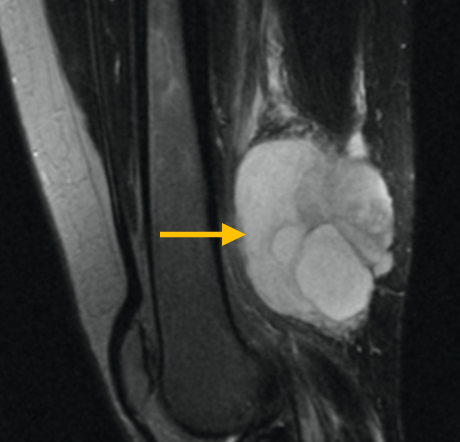

Round Cell Liposarcoma is a malignant, or cancerous, soft-tissue sarcoma that most commonly occurs in the deep tissues of the thigh, or other extremities. It is fairly aggressive and has a greater potential for metastasis.